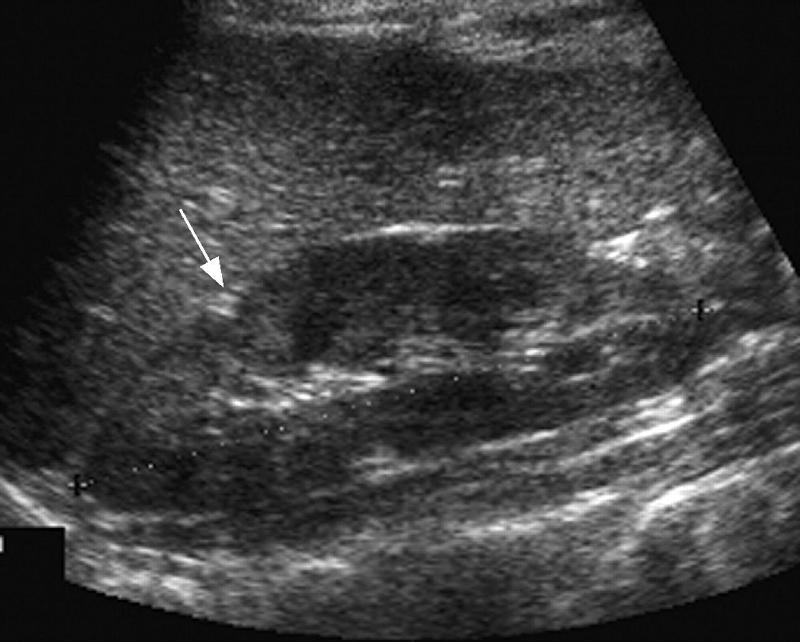

Pancreatic Psydocyst

Spherical fluid collection of pancreatic enzymes that arise from inflamatory, necrotic and hemorrhage processes of the pancrreas

persistently elevated amylase and lipase

Pancreatic Psydocyst

Spherical fluid collection of pancreatic enzymes that arise from inflamatory, necrotic and hemorrhage processes of the pancrreas

persistently elevated amylase and lipase

Pancreatic Psydocyst

Spherical fluid collection of pancreatic enzymes that arise from inflamatory, necrotic and hemorrhage processes of the pancrreas